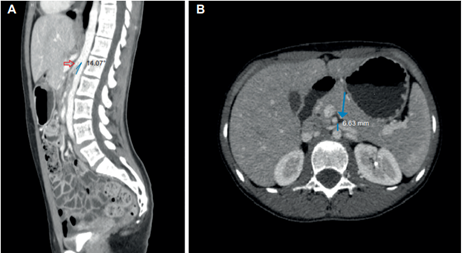

Adicionalmente fue valorada por psiquiatría, conceptuando que cursaba con cuadro ansioso, sin trastornos de la conducta alimentaria. Ante la poca claridad en los estudios, sin hallazgos relevantes en la batería de exámenes de laboratorio clínico, se decidió revisar junto con radiología las imágenes del TC trifásico realizado inicialmente, encontrando dos criterios imagenológicos para el diagnóstico de síndrome de pinza aortomesentérica: un ángulo aortomesentérico de 14,5° y una distancia aortomesentérica de 6,8 mm, asociados a dilatación duodenal leve (Figura 1); que sumados a la sintomatología permitieron hacer el diagnóstico definitivo de síndrome de Wilkie.

Es importante mencionar que en esta imagen se observó también una disminución del calibre de la vena renal izquierda, este hallazgo supuso contemplar la presencia del síndrome de cascanueces o nutcracker de manera concomitante. Dado que no se documentó hematuria, proteinuria, anemia, ni predominio de dolor en flanco izquierdo, no se profundizó en este aspecto y no se consideró necesario realizar otras imágenes para confirmar esta sospecha 7.